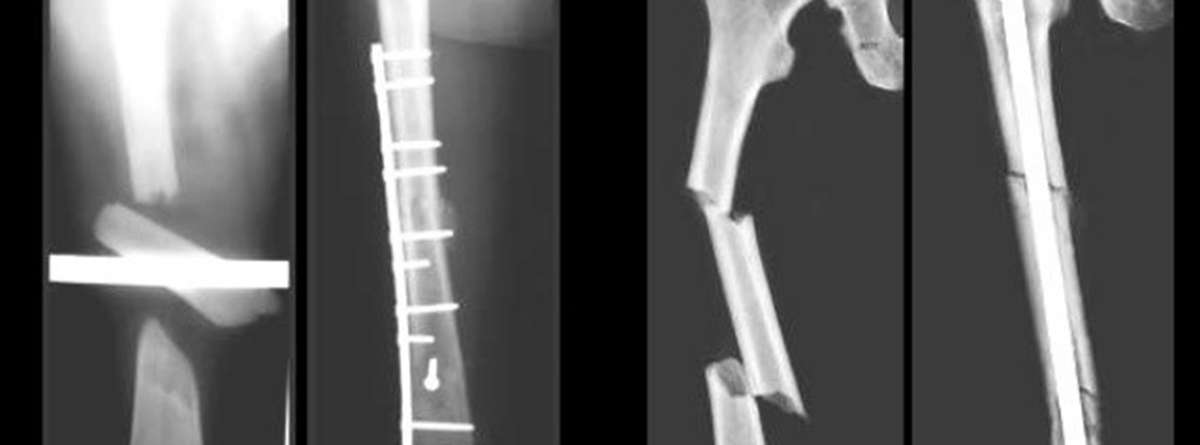

- Fijación estable: La ausencia de movimiento en el foco de fractura permite la calcificación del cayo óseo. Si existe movimiento, el cayo no adquiere la dureza suficiente ocurriendo la complicación llamada PSEUDOARTROSIS". Para lograr la fijación estable, algunos tipos de fractura pueden ser tratados con yesos o ferulas (inmovilizando hasta la articulación por encima y por debajo del hueso fracturado).

Otros tipos de fractura necesitan cirugía (llamada osteosíntesis) para ser fijadas internamente con placas, tornillos, clavos o con fijadores externos, porque los yesos o férulas no logran mantener la alineación, rotación y longitud del hueso afectado por la tensión de los músculos que pasan cerca de él.